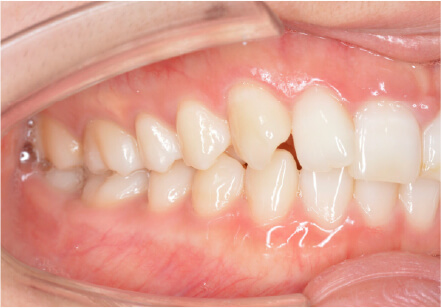

叢生の症例

13歳

男性

相談内容

マイオスマイルからの移行

カウンセリング・診断結果

治療内容・方法

全額アライナー矯正

術後の経過・現在の様子

クリアライナー使用

治療のリスク

痛み・歯根吸収・歯肉退縮・虫歯・後戻り

費用・治療期間

(インビザのみ)745,000円、1年11ヶ月